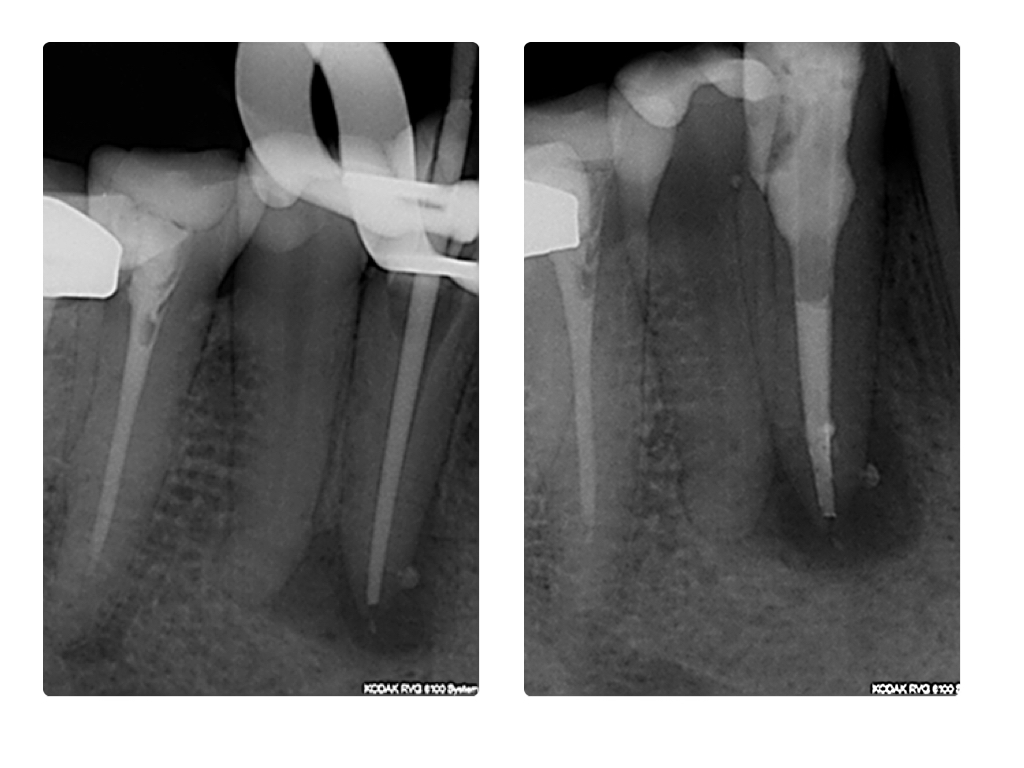

WS_Fallvorstellung8_15 8.002 Veröffentlicht 27. Juli 2015 am 1024 × 768 in Eckzahn im Recall Messaufnahme und WF-Kontrolle